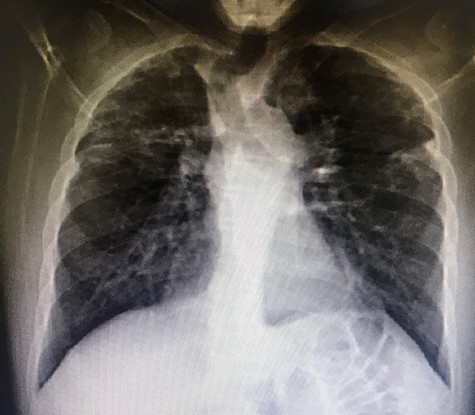

A 37-year-old Iraqi man was admitted to the hospital with progressive dyspnea on exertion occurring since 2 years and associated with dry cough. Patient was afebrile. The patient reported two episodes of severe dyspnea and low oxygen saturation occurring 1 month and 2 years ago. In both exacerbations, patient’s chest X-ray revealed left pneumothorax, and a tube thoracostomy was performed subsequently (Fig. 1). The patient served in the military service and was also a carpenter. Patient’s body mass index was 21 and his basal oxygen saturation was 97%. Physical exam showed flattened thorax and hypophonesis accentuated on the leftside during auscultation. At the admission, patient’s laboratory results were: pH = 7.43, PCO2 = 40, PO2 = 84, white blood cells count = 5350, neutrophils = 60, lymphocytes = 30, monocytes = 5.8, eosinophile = 2.1, hemoglobin = 14.1, hematocrit = 40, creatinine = 0.4, TSH = 0.51, free T4 = 11.53. A trans-thoracic echocardiography was made and did not show any significant finding. The purified protein derivative test results, the antinuclear antibody panel test and the rheumatoid factor detection test were negative. A video-assisted thoracoscopic surgery was performed to decorticate a restrictive layer of fibrous tissue overlying the lung, additionally to a wedge biopsy taken from the right apex. Histo-pathologic results reported a prominent interstitial fibrosis involving the subpleural and deep lung parenchyma with limited area of normal tissue intercepted between them (Fig. 2). No gronulomatous tissue was detected. The scarring tissue had a dense fibroelastotic appearance without active fibroblastic foci. Occasional dilated airspaces and ectatic lymphatic spaces were noted in the subpleural fibrotic parenchyma. Therefore, the diagnosis of IPPFE was made, and the other possible differential diagnoses are discussed below.